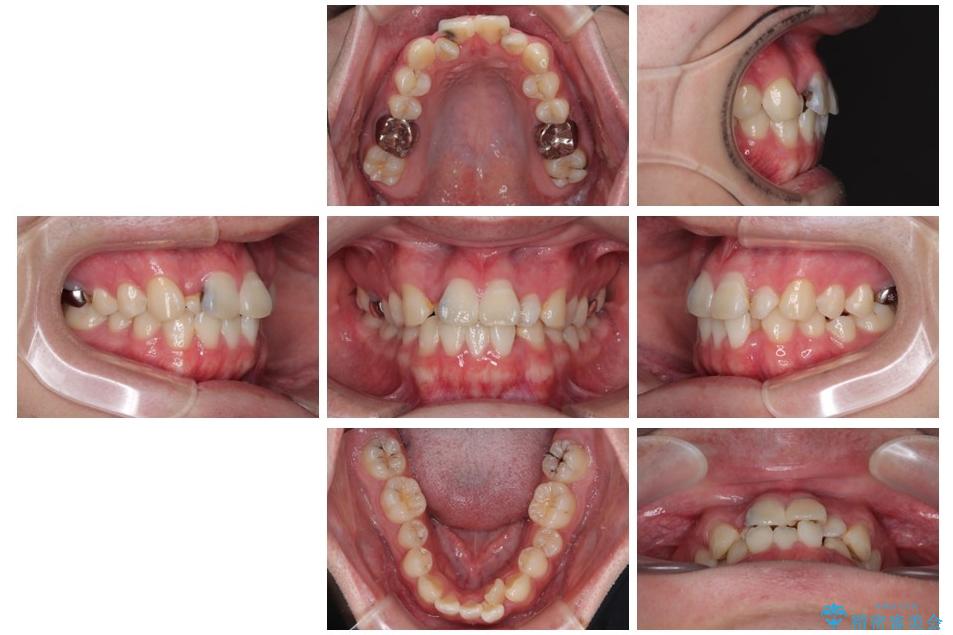

「歯並びがデコボコしていて、上下の中心がズレているのが気になる…」という悩みで来院された患者さまの症例をご紹介します。

初診時の状態

・上下ともに歯がきれいに並びきらず、がたつきが見られました。

・上下の前歯の中心(正中)がずれています。

・特に上顎の幅が狭いため、下顎の歯列も内側に入り込み、歯が並ぶスペースが不足していました。

治療前

• 1年でここまで変わる!歯列のがたつきと正中のズレを改善した矯正治療(メタルブラケット×MARPE) 治療前画像